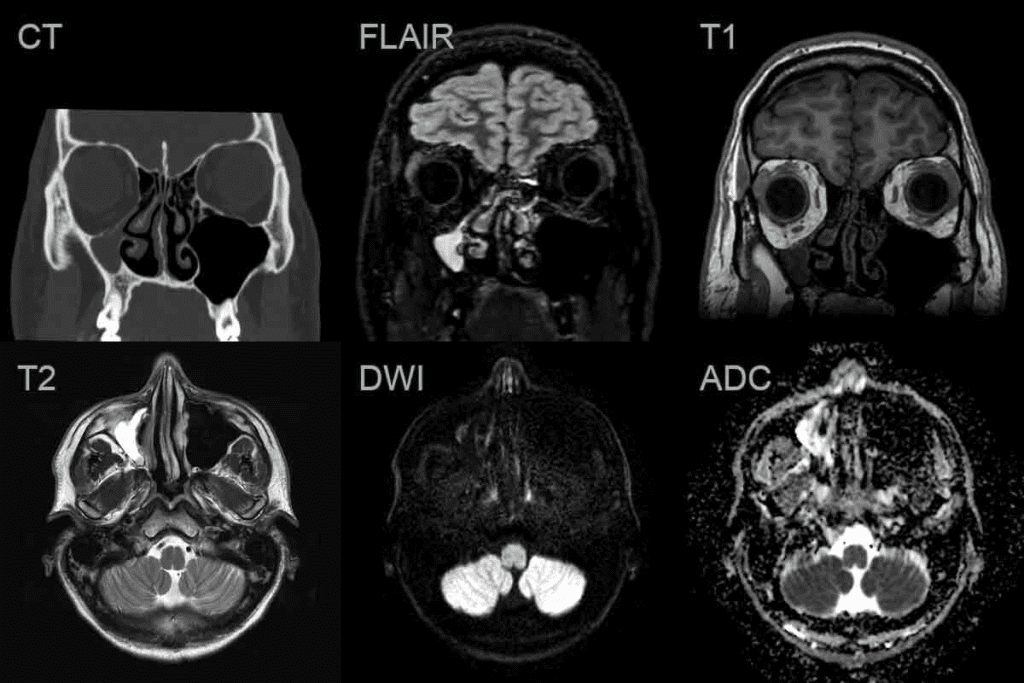

What a Healthy Sinus CT Scan Looks Like

A healthy sinus CT scan shows clear, air-filled sinuses. There are no signs of thickened mucosa or structural problems. This clarity helps us see how healthy sinuses work and drain properly.

Normal Findings on Sinus Imaging

Normal sinus imaging shows air-filled cavities. These cavities have a thin mucosa that’s not thick or inflamed. The lack of mucosal thickening is a sign of healthy sinuses.

Key features of normal sinus imaging include:

- Air-filled sinus cavities

- Thin mucosal lining without thickening

- No anatomical variants that could obstruct drainage

- Normal drainage pathways

Air-Filled Cavities Without Mucosal Thickening

In a healthy sinus CT scan, the sinus cavities are well-aerated. They are free of fluid or soft tissue opacification. The mucosa is not thickened, showing no inflammation or infection. This is different from sinusitis, where mucosal thickening and fluid buildup are common.

“The normal sinus mucosa is thin and almost imperceptible on CT scans, reflecting the healthy state of the sinuses.”

Absence of Anatomical Variants That Compromise Drainage

Anatomical variants like nasal septal deviation or Haller cells can block sinus drainage. In a healthy sinus CT scan, these variants are either not present or don’t affect drainage. The absence of such variants ensures proper drainage, lowering the risk of sinusitis.

The importance of a healthy sinus CT scan lies in its ability to:

- Confirm the absence of sinusitis

- Identify normal anatomical structures

- Rule out anatomical variants that could cause drainage issues